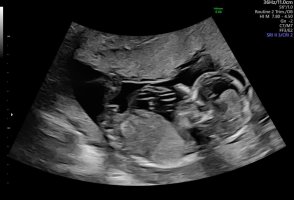

Noen som vil gjette her? 12+5. Usikker på om nub synes på disse bildene?

Jordmor tippet jente. Vi så nub mye tydeligere på skjerm. Ganske lang, rett og en liten vinkel oppover på tuppen. Da lå baby med god bøy på rygg. Andre steder så jeg den sto rett ut.

Senere sa jordmor det kunne se ut som gutt fra andre vinkler.